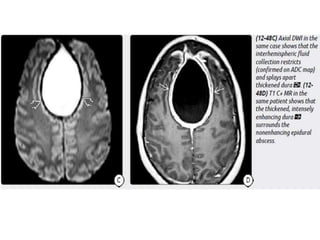

Imaging

NECT scans may be normal or show a hypodense extraaxial collection

that demonstrates peripheral enhancement on CECT.

Bone CT should be evaluated for signs of sinusitis and otomastoiditis.

MR is the procedure of choice for evaluating potential empyemas. T1

scans show an extraaxial collection that is mildly hyperintense relative to

CSF.

SDEs are typically crescentic and lie over the cerebral hemisphere. SDEs

often extend into the interhemispheric fissure but do not cross the midline.

EDEs are biconvex and usually more focal than SDEs. EDEs may cross

the midline, confirming their epidural location